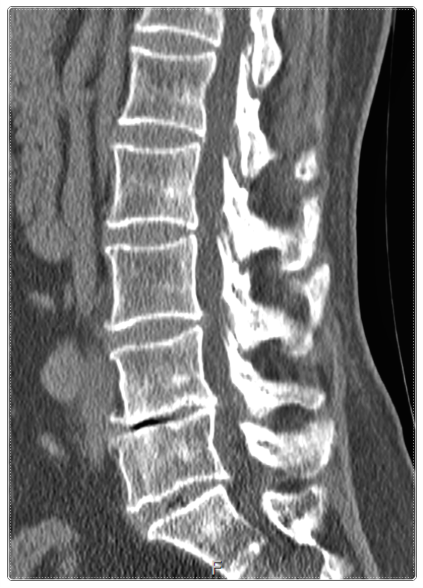

허리는 구조적으로 ‘S자 곡선’을 유지할 때 가장 안정적입니다.

이 곡선이 무너지면 디스크에 압력이 집중되어 다시 통증이 생기죠.

한의학에서는 허리디스크를 뼈, 근육, 인대, 신경의 조화가 깨진 상태로 봅니다.

즉, 단순히 구조적 문제만이 아니라 몸 전체의 균형과 순환을 함께 다루는 것이죠.

수술 후에는 디스크 주변 근육이 긴장하고 신경이 예민해져 통증이 쉽게 재발할 수 있습니다.